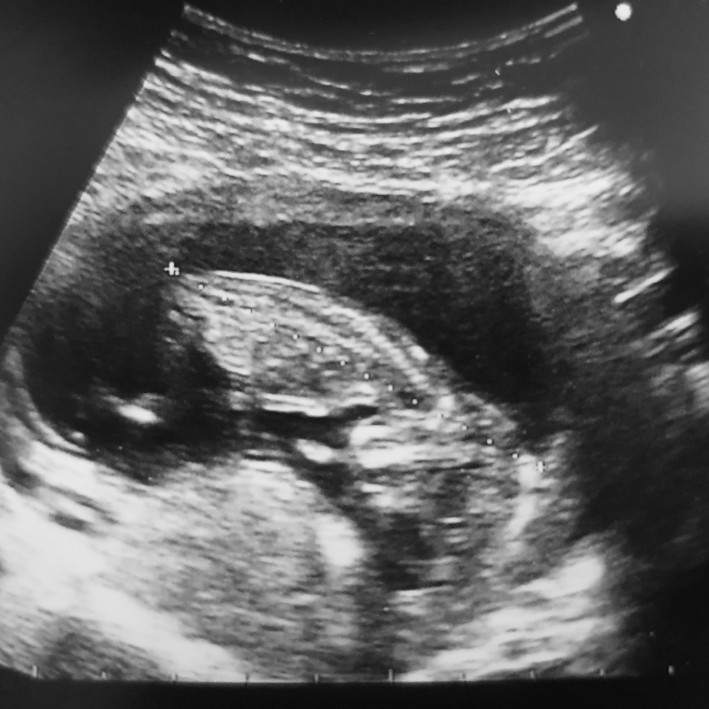

• Januari 2020

12 weken echo